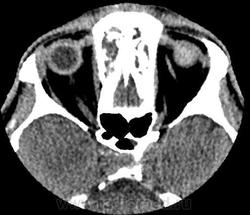

Обратите внимание на субдуральное пространство справа. Определяется тонкое пластинчатое скопление патологического изоденсного содержимого над конвекситальными отделми правой гемисферы большого мозга. Слева оболочечные пространства выражены обычно.

Каюсь, я так сосредоточилась на костных изменениях, что факт наличия этого содержимого в третьем часу ночи был мной упущен.

Была произведена фронтотомия, эвакуировано гнойное содержимое. Пациент в сознании, актвен, был госпитализирован в ЛОР-отделение. Через 3 дня клиническое ухудшение состояния, сопор. Выполнено контрольное КТ головного мозга с контрастным усилением.

Обнаружено: состояние после фронтотомии;

-над лобной, височной и теменной долями правого полушария большого мозга определяется скопление патологического содержимого плотностью до +20HU, размерами 122х14х98мм(V~87см3)- субдуральная эмпиема, размеры ранее описываемого участка гиподенсной плотности в полюсно-базальных отделах правой лобной доли (+25+30Hu), увеличились до 36х11мм. Смещение срединных структур влево до 10мм.